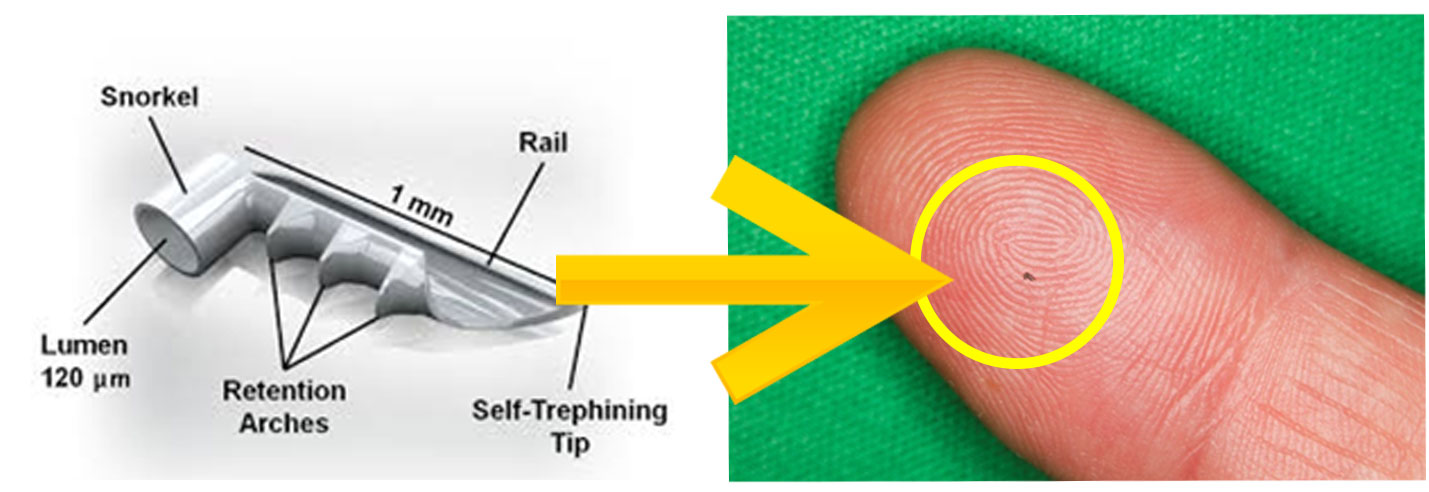

iStent®は開放隅角緑内障に対して眼圧を下降させる極低侵襲緑内障手術の際に使用されるMIGS(micro-invasive glaucoma surgery)デバイスです。単独での手術の際は自由診療となりますが、白内障手術と同時に行われる際には保険診療となります。

iStent®は、長さ横1mm縦0.12mmの非常に小さいデバイスです。緑内障手術は線維柱帯切除やEx-PRESS手術など各種の手術がありますが、今までの手術は目への侵襲が大きい手術でありました。

白内障手術の際に2.4mmの白内障手術創口からiStent®を線維柱帯にインプラントして、房水流出を妨げている線維柱帯に対して排出を改善し眼圧を下降させます。その為、侵襲の非常に少ない緑内障手術、極低侵襲緑内障手術として注目されております。臨床試験の結果では眼圧の下降と緑内障治療薬の低減が示されています。日本眼科学会HP[http://www.nichigan.or.jp/member/guideline/iStent.jsp]に詳細と論文がありますので、メリットデメリットなどご参考にして頂けますと幸いです。